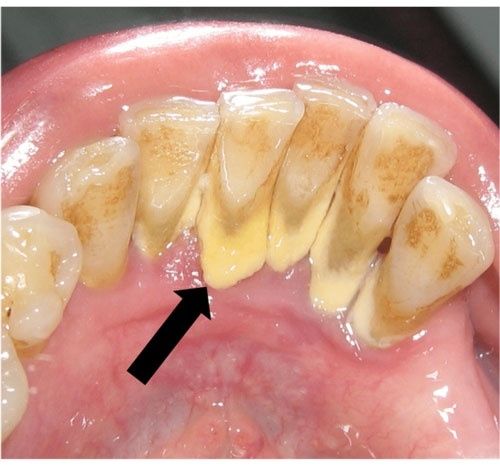

Vôi răng (cao răng) là lớp mảng bám cứng, hình thành từ thức ăn thừa, vi khuẩn và khoáng chất trong nước bọt. Nếu không được loại bỏ bằng cách đánh răng thường xuyên và đúng cách, mảng bám sẽ khoáng hóa thành vôi răng bám chắc vào thân răng và dưới nướu.

Viêm nướu, viêm nha chu, làm tụt lợi, răng lung lay

Tăng nguy cơ sâu răng, đặc biệt ở vùng cổ răng

Gây mất thẩm mỹ (vôi răng vàng, nâu, đen…)

Là nguyên nhân tiềm ẩn gây mất răng sớm